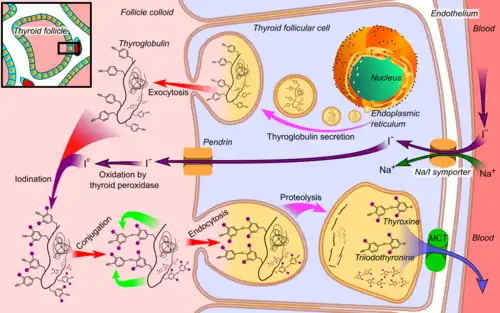

Hormone production

- Thyroglobulin is synthesized in the rough endoplasmic reticulum and follows the secretory pathway to enter the colloid in the lumen of the thyroid follicle by exocytosis.

- Meanwhile, a sodium-iodide (Na/I) symporter pumps iodide (I−) actively into the cell, which previously has crossed the endothelium by largely unknown mechanisms.

- This iodide enters the follicular lumen from the cytoplasm by the transporter pendrin, in a purportedly passive manner.

- In the colloid, iodide (I−) is oxidized to iodine (I0) by an enzyme called thyroid peroxidase.

- Iodine (I0) is very reactive and iodinates the thyroglobulin at tyrosyl residues in its protein chain (in total containing approximately 120 tyrosyl residues).

- In conjugation, adjacent tyrosyl residues are paired together.

- The entire complex re-enters the follicular cell by endocytosis.

- Proteolysis by various proteases liberates thyroxine and triiodothyronine molecules, which enters the blood by largely unknown mechanisms.

The thyroid hormones are created from thyroglobulin. This is a protein within the colloid in the follicular lumen that is originally created within the rough endoplasmic reticulum of follicular cells and then transported into the follicular lumen. Thyroglobulin contains 123 units of tyrosine, which reacts with iodine within the follicular lumen.[34]

Iodine is essential for the production of the thyroid hormones. Iodine (I0) travels in the blood as iodide (I−), which is taken up into the follicular cells by a sodium-iodide symporter. This is an ion channel on the cell membrane which in the same action transports two sodium ions and an iodide ion into the cell.[35] Iodide then travels from within the cell into the lumen, through the action of pendrin, an iodide-chloride antiporter. In the follicular lumen, the iodide is then oxidized to iodine. This makes it more reactive,[33] and the iodine is attached to the active tyrosine units in thyroglobulin by the enzyme thyroid peroxidase. This forms the precursors of thyroid hormones monoiodotyrosine (MIT), and diiodotyrosine (DIT).[2]

When the follicular cells are stimulated by thyroid-stimulating hormone, the follicular cells reabsorb thyroglobulin from the follicular lumen. The iodinated tyrosines are cleaved, forming the thyroid hormones T4, T3, DIT, MIT, and traces of reverse triiodothyronine. T3 and T4 are released into the blood. The hormones secreted from the gland are about 80–90% T4 and about 10–20% T3.[36][37] Deiodinase enzymes in peripheral tissues remove the iodine from MIT and DIT and convert T4 to T3 and RT3. [34] This is a major source of both RT3 (95%) and T3 (87%) in peripheral tissues.[38]